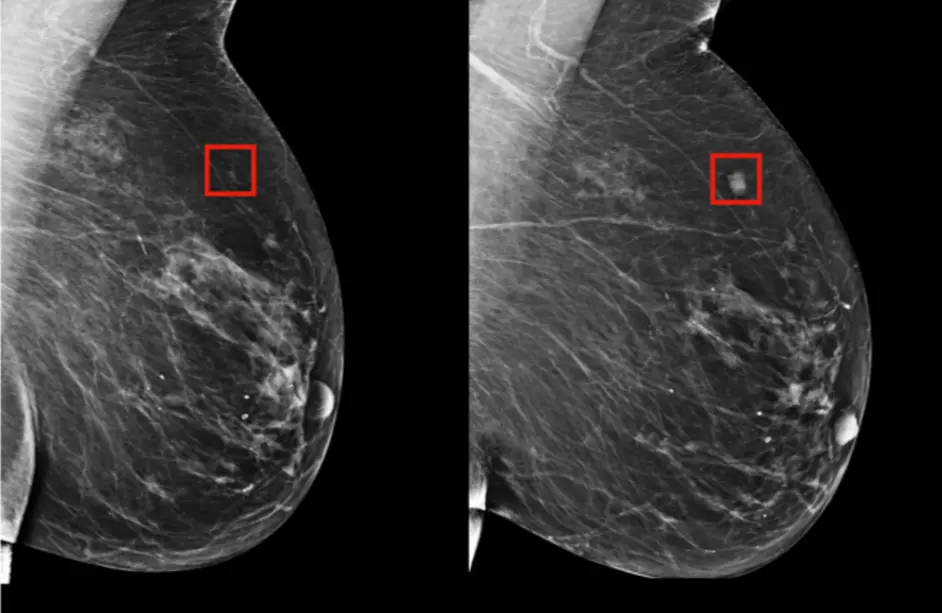

Meme Kanseri Taramasında Yapay Zeka

Meme Kanseri nedir? Belirtileri nelerdir?